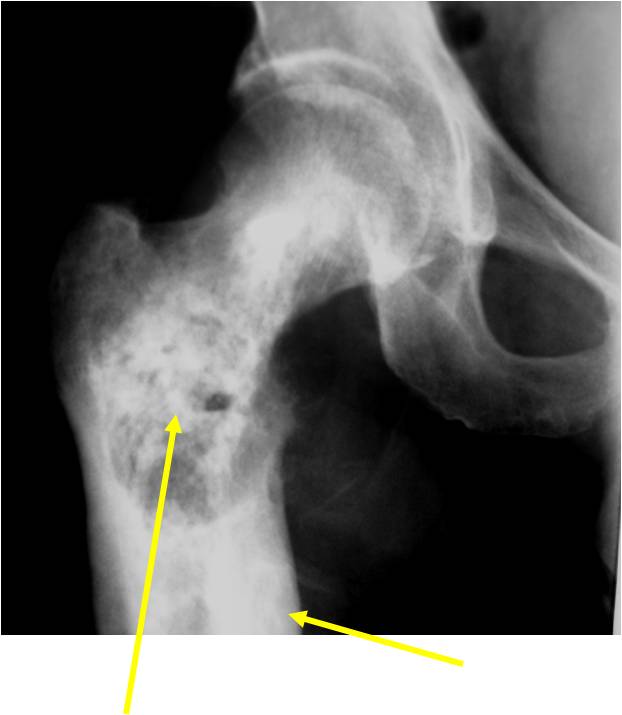

Radiology emulates pathology: Biphasic Tumor

- One region low grade chondrosarcoma

- Second more aggressive area with bone destruction, lysis of calcification, soft tissue mass

- Cortical permeation and a soft tissue mass in 70% of cases

Ill-defined, lytic intraosseous lesion

- Or extraosseous soft tissue mass

- Devoid of calcifications in continuity with lesions having the features of a cartilaginous tumor

Characteristically abrupt transition between chondroid tumor and dedifferentiated, lytic component

Bone may be expanded and adjacent cortex thickened

(Right Arrow)Aggressive Lytic Area (Dedifferentiated Sarcomatous Component) Cortical Destruction Soft Tissue Mass without Calcification